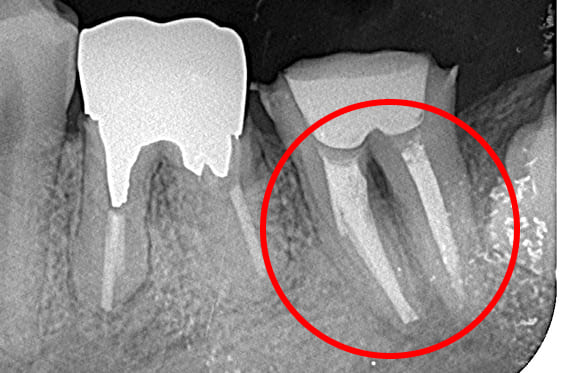

01 左下7の近心根にエンジンファイルの破折

02 ファイル除去時

※根尖周囲の透過像はまだ残存

03 最終の根充剤を充填

※根尖透過像が小さく治癒方向へ向かっている